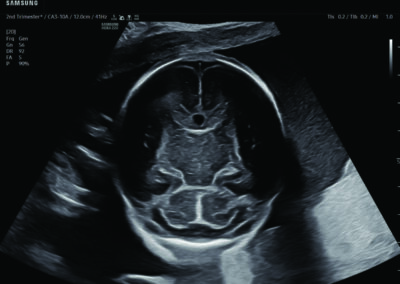

Comprehensive, advanced and expert MFM care for high-risk pregnancies

- Neural tube defects

- Fetal anomalies